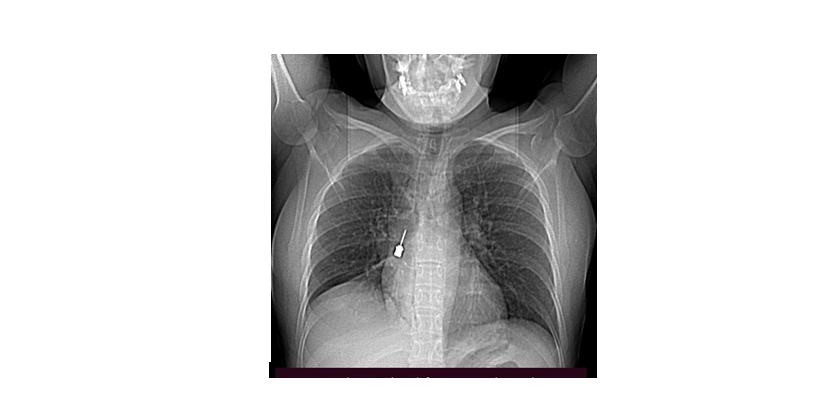

REGGIO CALABRIA Delicatissima procedura endoscopica effettuata nelle scorse settimane al Grande Ospedale Metropolitano di Reggio Calabria. Il Direttore dell’UOC di Chirurgia Toracica, Baldassare Mondello, insieme alla sua équipe, ha estratto in urgenza per via broncoscopica un cacciavite odontoiatrico accidentalmente inalato da una giovane donna. La paziente è giunta al Pronto Soccorso del G.O.M. esibendo un esame di diagnostica per immagini (Tomografia Computerizzata) eseguito a causa di una tosse persistente e di un forte dolore a livello toracico.

La TC mostrava la presenza di un corpo estraneo metallico pericolosamente incastrato nel bronco lobare inferiore del polmone destro e un concomitante pneumomediastino, ossia la presenza di aria nello spazio compreso fra i due polmoni. Prontamente ricoverata, la paziente è giunta in sala operatoria ove è stata sottoposta in urgenza all’intervento. Il decorso postoperatorio, gestito dalla validissima équipe della U.O.S.D. Terapia Intensiva Post Operatoria (T.I.P.O.) diretta dal Massimo Caracciolo, è stato regolare e la paziente è stata dimessa in ottime condizioni. Il personale che ha coadiuvato Mondello nell’intervento: Massimino Messinò (medico in formazione), anestesisti, Lilly Gatto e Leonardo Cosenza. Personale del Blocco Operatorio: CPS Fortunato Quattrone, CPS Angela Fiozzo e CPS Paolo Pennestrì. (redazione@corrierecal.it)